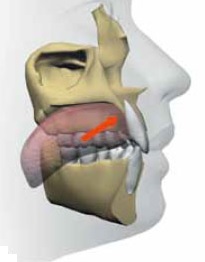

舌体は上あごの口蓋に軽く吸い付いて挙上しているのが正常な状態です。もちろん上下唇は閉じています。

舌が挙上している状態では口呼吸ができません。つまり舌が持ち上がっていることは鼻呼吸するための必要条件なのです。

ところが舌小帯が短かったりして舌の挙上が常時妨げられている場合、舌はほとんど動かないために下アゴの歯列内に収まったままの状態で、歯の痕がつくだけでなく舌本来の機能をほとんど果たしていません。

舌体のサイドに歯の痕がくっきりとついている場合は、舌が大きい場合もありますが、下あごの小・大臼歯が内側に倒れて歯列の幅が狭くなっている場合も多いのです。さらには個々の小・大臼歯が上から常に舌に押され続けることで前方に倒されてしまって、前歯にしわ寄せがきて歯並びが乱れることが考えられます。(左下図の白矢印)